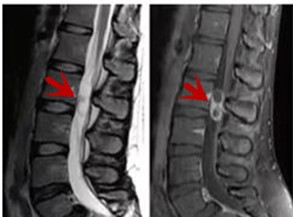

利器三:MRI(核磁共振)

MRI利于磁場(chǎng)和射頻脈沖使體內(nèi)的氫原子核發(fā)生磁共振現(xiàn)象而產(chǎn)生的圖像,對(duì)軟組織的分辨率很高,對(duì)于脊髓、椎間盤、神經(jīng)、血管、韌帶、骨髓、腰部肌肉及周圍軟組織有很好的顯示效果,可以清晰的顯示腰椎間盤突出對(duì)硬膜囊、神經(jīng)根壓迫程度,以及骨折是陳舊還是新鮮,同時(shí)在脊髓病變(如脊髓損傷、髓內(nèi)出血或腫瘤)、椎管內(nèi)膿腫/血腫、椎旁肌肉軟組織病變等方面也具有優(yōu)勢(shì),但是檢查時(shí)間較長(zhǎng),部分患者可能因體內(nèi)金屬植入物(如心臟起搏器、人工耳蝸等)而無(wú)法進(jìn)行檢查。

箭頭提示腰椎管內(nèi)腫瘤

紅色箭頭提示新鮮骨折,黃色箭頭提示陳舊性骨折